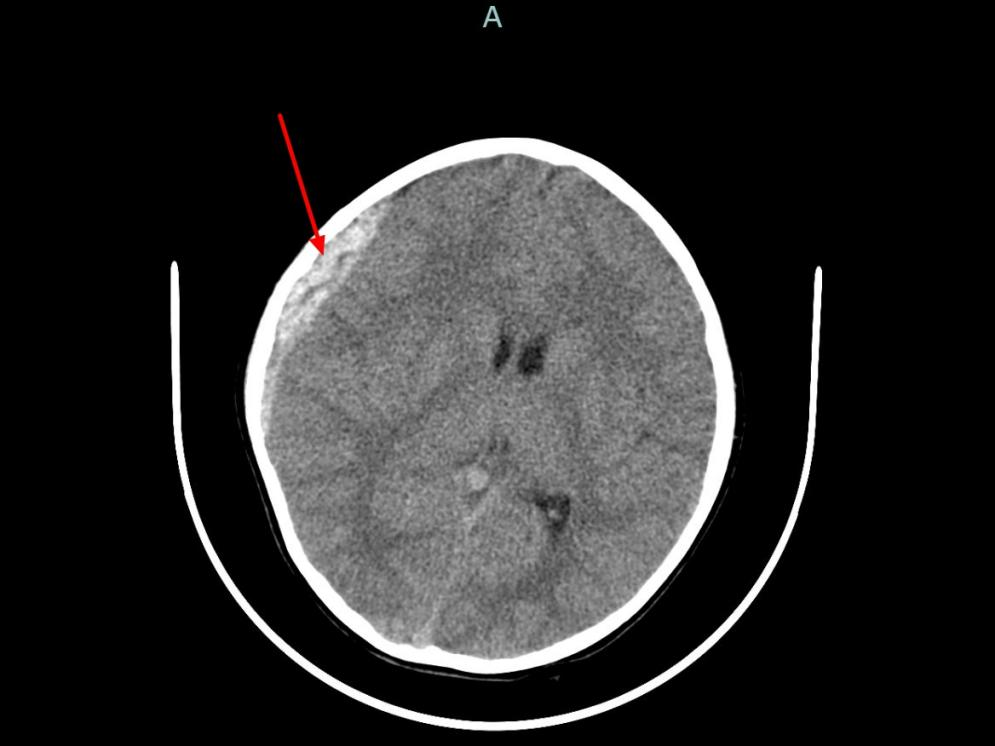

日前,6岁的童童(化名)被推进了杭州市儿童医院急诊抢救大厅,右侧头皮血肿,恶心、呕吐,嘴里喊着“头痛”……原来,半小时前他坐的电瓶车被小汽车撞倒,头部磕到地面,糟糕的是,当时孩子没有戴头盔!经验丰富的急诊团队心中警铃大作,迅速完成一系列操作。10分钟完成头颅CT检查,影像清晰显示右额顶骨骨折,右侧颞顶部硬膜外血肿,中线结构明显偏移,随时可能发生脑疝!

时间就是生命,此时童童喷射性呕吐加剧,意识也逐渐模糊。杭州市儿童医院神经外科李奇峰副主任医师紧急赶到,孩子被推进了手术室……好在抢救及时,术后CT复查显示颅内压显著降低,脑组织复位良好。PICU、神经外科、麻醉科、手术室多科协作,童童顺利化险为夷。